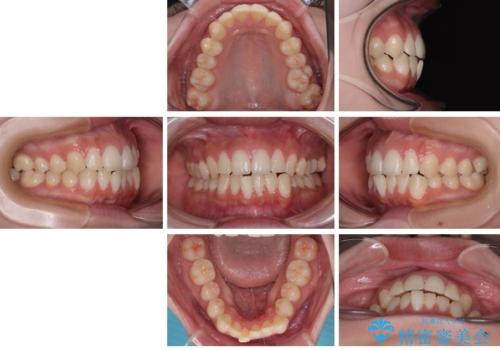

- 今回は「下の前歯のデコボコを治したい」と来院された患者様の症例をご紹介します。

患者様は「目立たない装置で矯正したい」との希望があり、当院では透明なマウスピース型矯正装置(インビザライン)による治療を提案しました。

診察してみると、下の前歯が並ぶためのスペースが足りないことが、歯並びがデコボコしている原因でした。

そこで今回は、以下の2つの方法を組み合わせて治療を行いました:

下の前歯の歯と歯の間をわずかに削ってスペースを作る(IPR)

奥歯を後ろに動かして、前歯が並ぶためのスペースを確保する

この計画により、デコボコだった下の前歯はしっかりと並び、わずか1年で治療を終えることができました

見た目が気にならないマウスピース矯正だったこともあり、患者様にも大変ご満足いただけました。